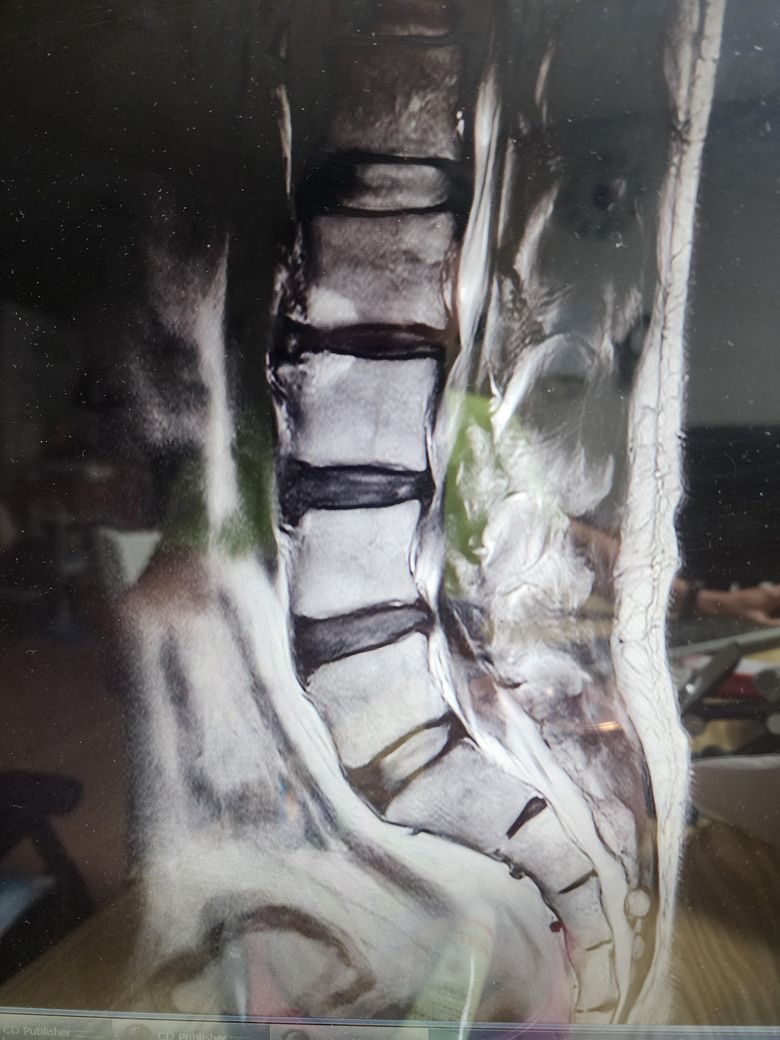

• 4번 째 사진

보여주신 MRI 상에는 척추관 협착증은 전혀 보이지 않습니다.

아래 첫번째 그림에 보시는것과 같이 B에서 보이듯이 검정색 신경뿌리 주변의 하얀색 뇌척수액이 공간 없이 비좁아지는 정도는 되어야 척추관 협착증이라고 이야기할 수 있을텐데 보여주신 MRI 에는 이런 모습은 없습니다.

추간판 공간이 줄어들어있고, 디스크 증상처럼 돌출이나 퇴행적 변화가 관찰되는 것으로 생각되는데요, 결국에 수술적 치료를 하더라도 보존적인 치료법을 먼저 시행하여 경과를 살펴보고 차도가 없는 경우 수술을 고려하는 것이 많기 때문에 우선 보존적 치료가 가능한 경우라면 수술은 조금 더 나중에 고려를 해보시는 것도 좋겠습니다. 수술을 고려중이신 경우에는 가능한 여러 전문의들의 의견을 들어보시는 것도 좋은 방법이 될 수 있겠습니다.